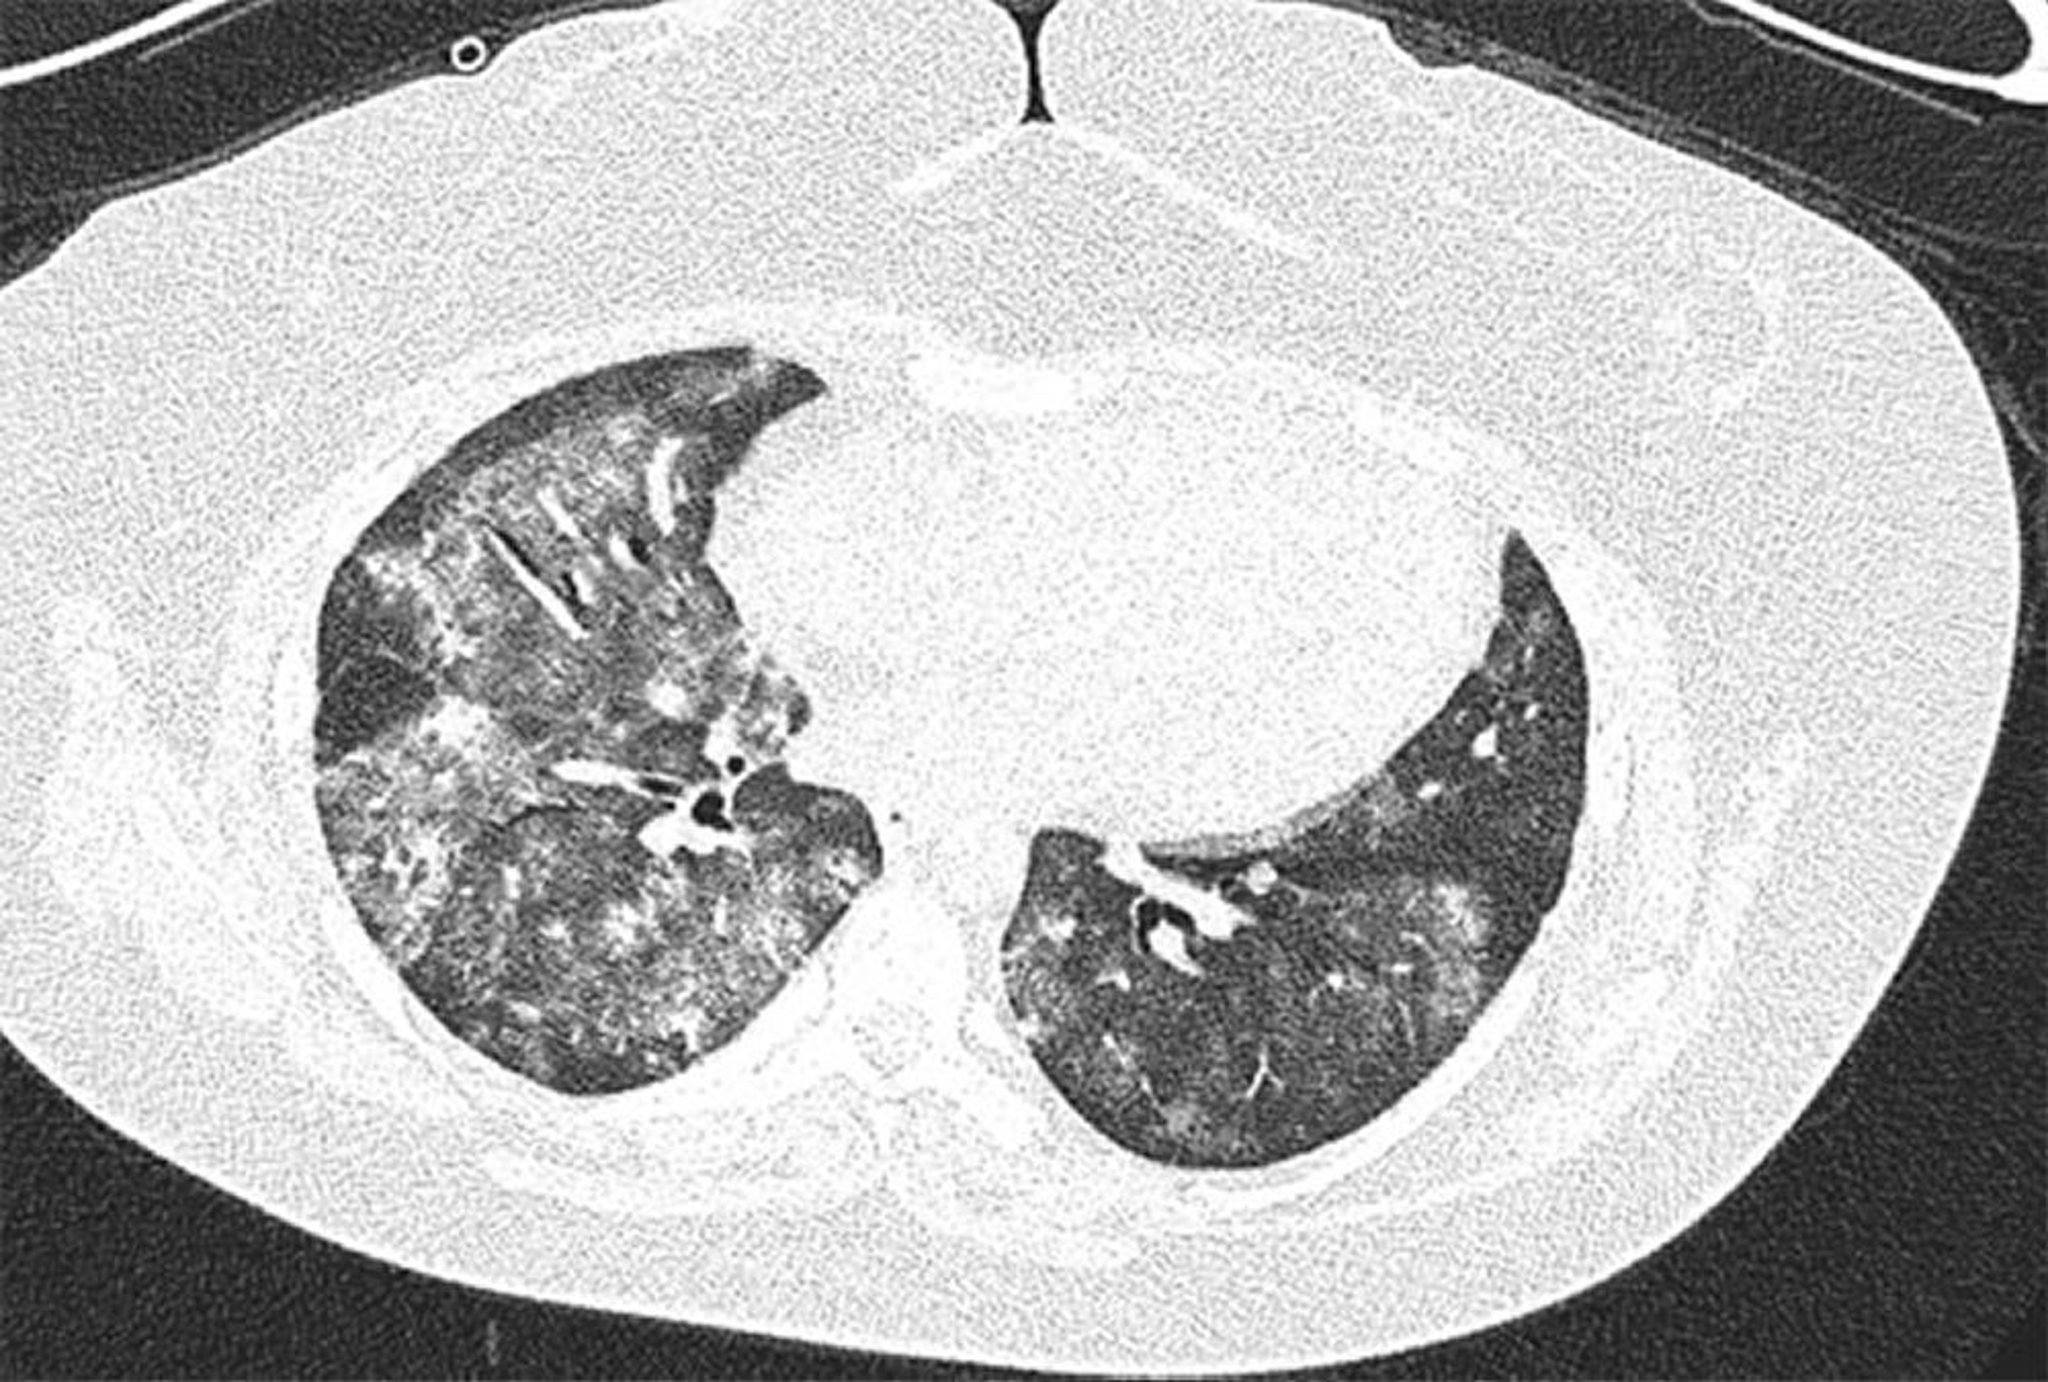

Hémorragie alvéolaire diffuse

Image TDM à haute résolution d'une femme de 28 ans atteinte d'un syndrome des anti-phospholipides avec hémorragie alvéolaire diffuse récurrente. L'image montre des opacités en verre dépoli alvéolaires bilatérales et inégales avec épargne sous-pleurale. Le lavage bronchoalvéolaire a confirmé l'hémorragie alvéolaire.

Image courtoisie de Joyce Lee, MD.